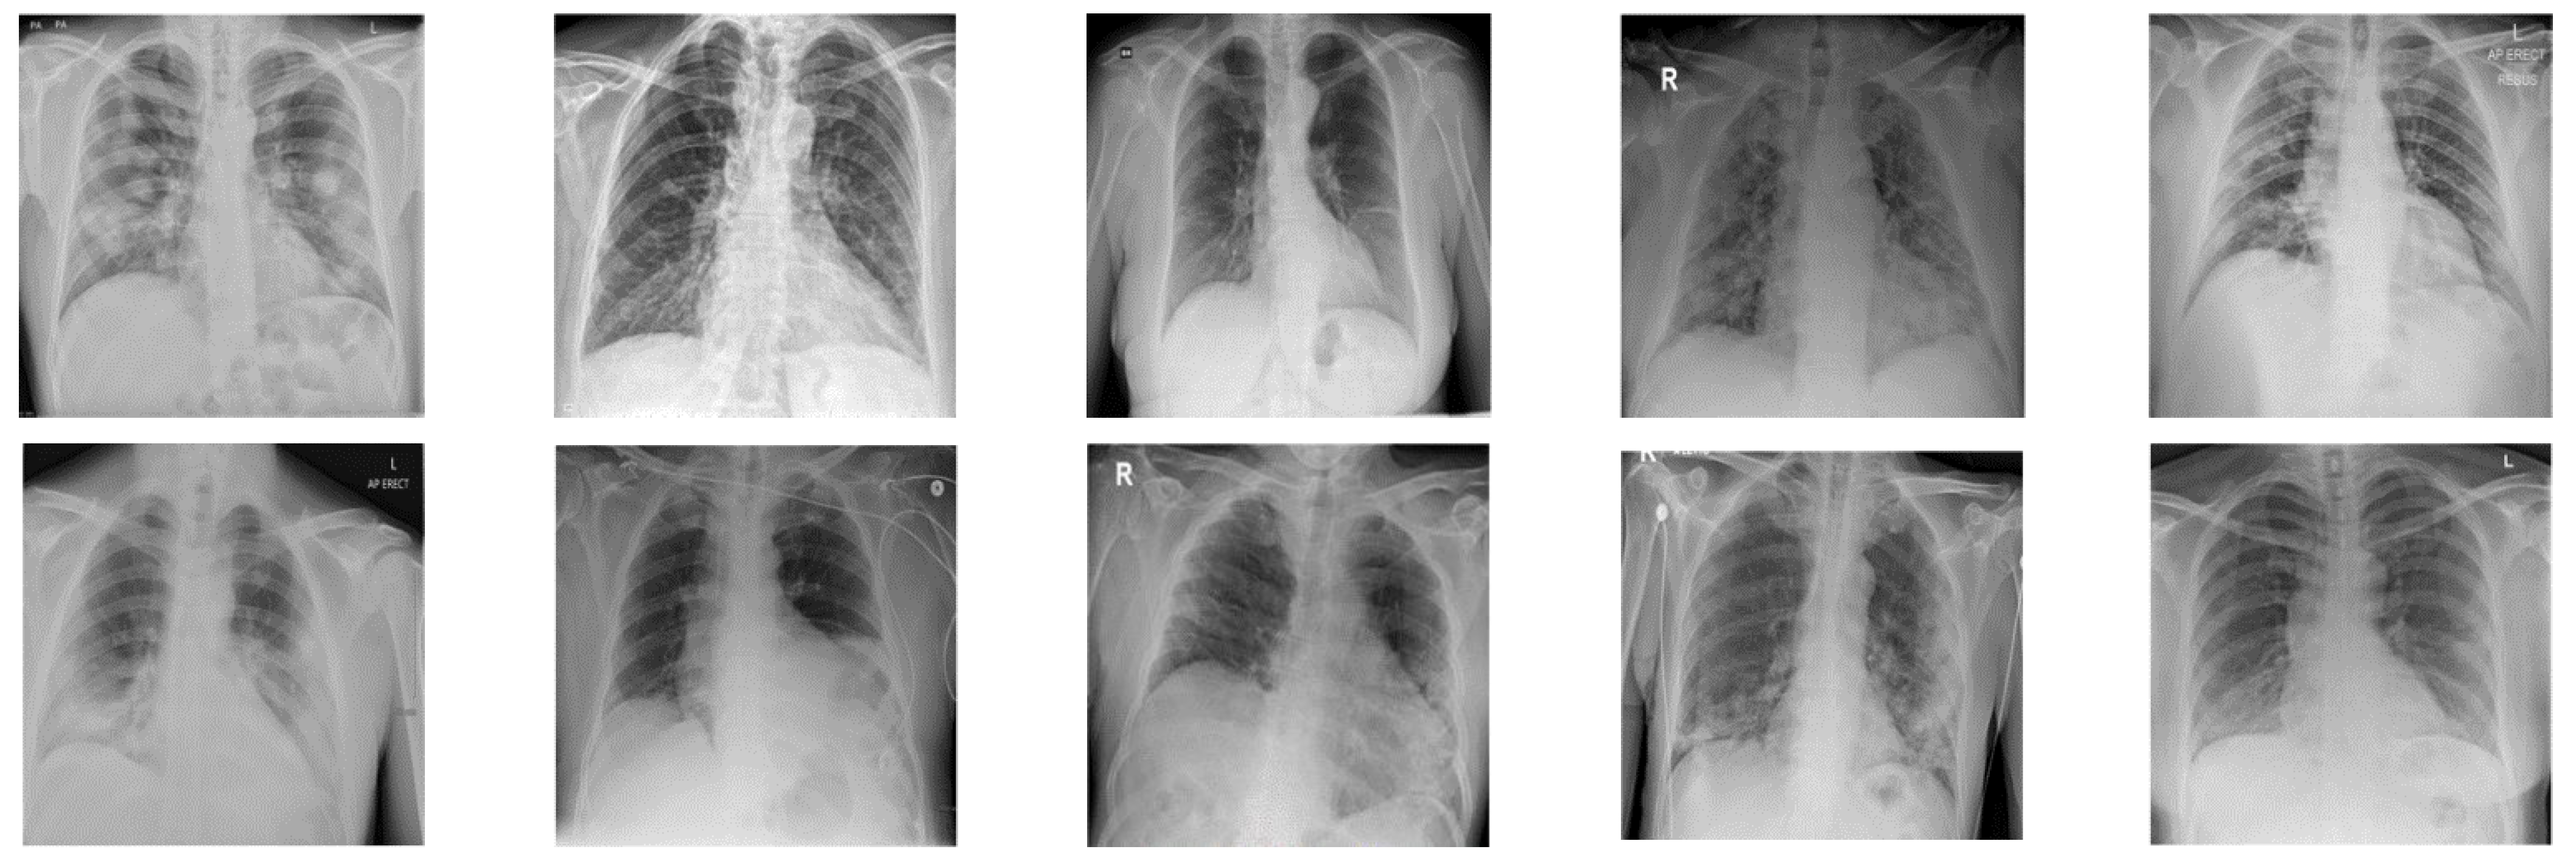

In this paper, in order to evaluate the proposed cryptographic method, multiple medical images and benchmarks have been adopted. The images tested in this section contain a variety of standard benchmark images and medical images including CT and X-ray. In Figure 11, 10 images of standard benchmarks for conducting experiments are displayed. Also, shown in Figure 12 are X-ray images of COVID-19 patients. Finally, 10 CT images of patients with COVID-19 are used for the final tests, as shown in Figure 13.

X-ray images used in the proposed method.